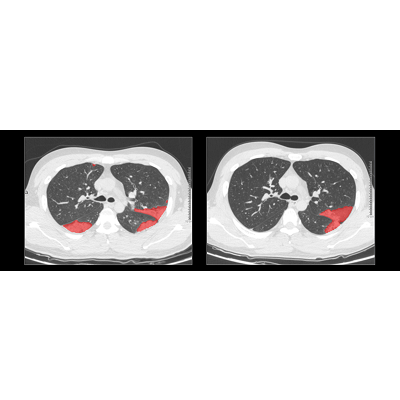

联影智能CT肺炎智能分析系统可自动检出多种肺炎相关征象,高灵敏识别早期微小病变;精准勾画病灶区域,与医生勾画误差<1%;提供预读分诊功能,根据胸部CT特征智能计算,优先筛选出重症患者,实现患者分流。提供病灶的成分分析,对病灶进行多维量化分析。提供智能随访对比,直观比较患者多次CT检查中的病灶变化,助力医生准确衡量患者病情进展。

联影智能CT肺炎智能分析是业界首款融合肺炎整体与局部影像特征的AI全流程解决方案,基于uAI独创分割引擎,该AI系统对新冠病毒感染病灶勾画重合率接近90%,全肺感染百分比量化误差小于1%,可将5至10分钟的CT阅片缩短至1分钟以内,阅片效率提升近十倍。同时还可有效助力医生甄别疑似病例、合理分流患者。

联影智能CT肺炎分析系统的引入,为医生提供了高精度诊断支持,自动标记病灶、显示感染范围和病变程度,极大地提升了鉴别分析效率,满足临床精准需求,并在筛查、诊断和预后中发挥关键作用,获医生高度认可。“不仅符合预期,更超出预期!”放射科专家评价说:“uAI可在新型冠状病毒筛查、诊断、预后等各个环节发挥作用,并在磨玻璃病变识辩、分割方面,满足临床对精准的需求。”